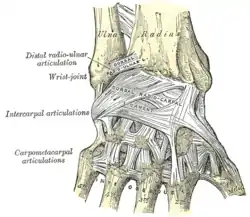

The midcarpal joint is the S-shaped joint space separating the proximal and distal rows of carpal bones. The intercarpal joints, between the bones of each row, are strengthened by the radiate carpal and pisohamate ligaments and the palmar, interosseous, and dorsal intercarpal ligaments. Some degree of mobility is possible between the bones of the proximal row while the bones of the distal row are connected to each other and to the metacarpal bones —at the carpometacarpal joints— by strong ligaments —the pisometacarpal and palmar and dorsal carpometacarpal ligament— that makes a functional entity of these bones. Additionally, the joints between the bases of the metacarpal bones —the intermetacarpal articulations— are strengthened by dorsal, interosseous, and palmar intermetacarpal ligaments.[6]

Wrist joint. Deep dissection. Posterior view.

Wrist joint. Deep dissection. Posterior view. Wrist joint. Deep dissection. Posterior view.

Wrist joint. Deep dissection. Posterior view. Wrist joint. Deep dissection.Anterior, palmar, view.

Wrist joint. Deep dissection.Anterior, palmar, view. Wrist joint. Deep dissection.Anterior, palmar, view.

Wrist joint. Deep dissection.Anterior, palmar, view.